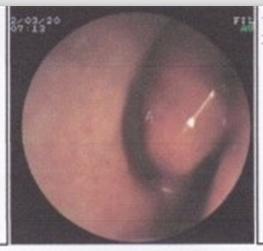

传统的治疗鼻甲肥大的方法,如冷冻、激光、微波、下鼻甲部分切除手术等均破坏了正常的鼻粘膜结构,影响鼻腔的生理功能。随着对鼻腔生理功能的逐步认识和重视,下鼻甲手术应向着“保护下鼻甲功能的同时将其缩小到最佳体积”的目标不断进取。

新一代低温等离子消融修复术——高效治疗鼻甲肥大,疗效显着、确切

贵阳耳鼻喉医院耳鼻咽喉诊疗中心耳鼻咽喉科引进国际先进的新一代等离子消融修复术疗法,实现对给鼻甲肥大的逆转治疗,给广大鼻甲肥大患者带来健康福音!此疗法在尽可能保护鼻甲功能的前提下进行鼻甲减肥,改善饮鼻甲肥大引起的鼻塞,呼吸不畅。